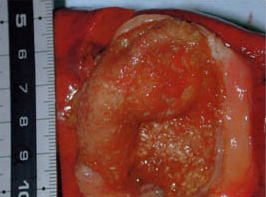

手前が摘出した「胆のう」後側が「肝臓」の一部。

「胆のう」の上部の腫れているところが腫瘍部。